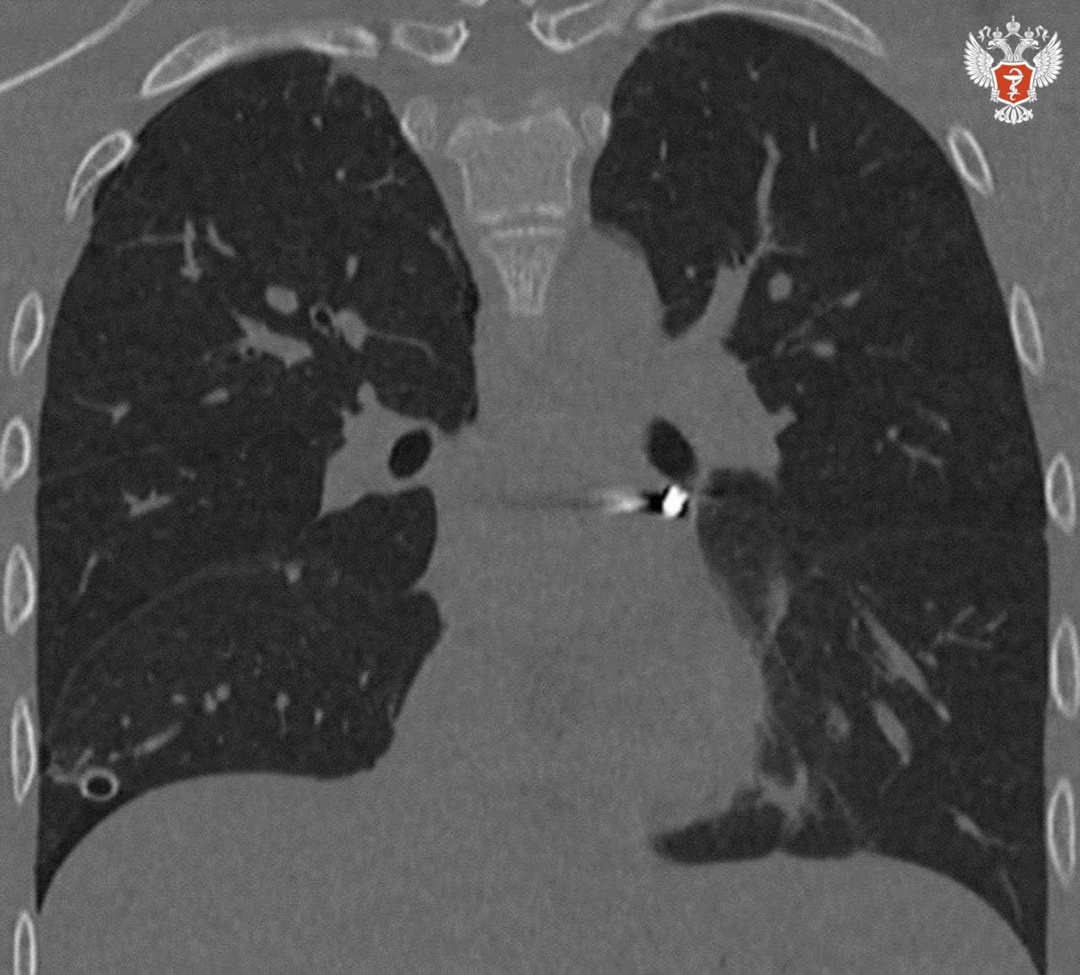

➡️ В ходе обследования врачи выявили крайне опасное расположение инородного тела в непосредственной близости от сердца: в полости перикарда – наружной оболочки сердца. Врачи приняли решение о проведении операции.

— Инородное тело мигрировало в опаснейшую зону — между легочными венами у задней поверхности предсердия. В ходе вмешательства нам удалось извлечь инородное тело без единого разреза, — рассказывает заведующий отделением детской хирургии №2 Никита Степаненко.